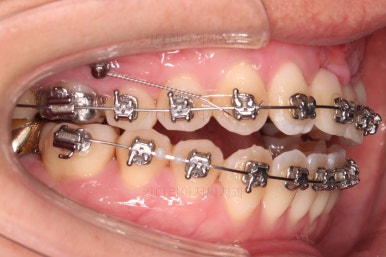

윗니 어금니를 뒤로 밀면서 앵글씨 2급 부정교합을 개선해 주고, 높낮이를 조절하면서 개방교합을 개선해 줍니다.

개방교합도 많이 다물어졌고, 2급 부정교합도 매우 많이 개선되었네요.

임플란트 가능 시점이 점점 다가오는데요.

임플란트를 한 번 하게되면 많은 치아 움직임은 없어야 되기 때문에, 앞니의 높이, 입매, 교합 등등 모든 점에서 평가가 진행됩니다.

임플란트 뿌리 부분부터 식립이 되었습니다.

처음에는 언급드린대로 앞니 잇몸을 아래로 내리지 못한 점이 아쉽지만 발치 시점을 잘 선택하여 최대한 잇몸뼈를 보존했다는 점에서 만족스러웠습니다.

임플란트 머리 부분이 올라가기까지 기다리는 동안 좀 더 부산개방교합 디테일을 맞추고 마무리를 합니다.